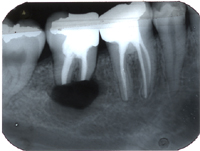

Eine 31 Jahre alte Patientin hatte akute Schmerzen am zweithintersten Backenzahn im Unterkiefer rechts und kam am 26. März 1980 zu uns in die Praxis.

Im Röntgenbild von Abb. 3 ist ein gut erbsengrosses Granulom (Pfeil) an der Wurzelspitze eines toten, devitalen Zahnes feststellbar. Die Patientin wünschte die Erhaltung des Zahnes, zumal auch der vordere Nachbarzahn marktot und beherdet war. Abb. 4 zeigt das Röntgenbild nach der Wurzelfüllung.

Ein halbes Jahr später hat die Patientin sich dazu entschlossen, den vorderen beherdeten Zahn auch endodontisch behandeln zu lassen. An Abb. 5 wird im Röntgenbild die Wurzellänge mit Instrumenten bestimmt. Man gewinnt auch den Eindruck, dass der bereits vor einem halben Jahr wurzelbehandelte Zahn in Abheilung sei.